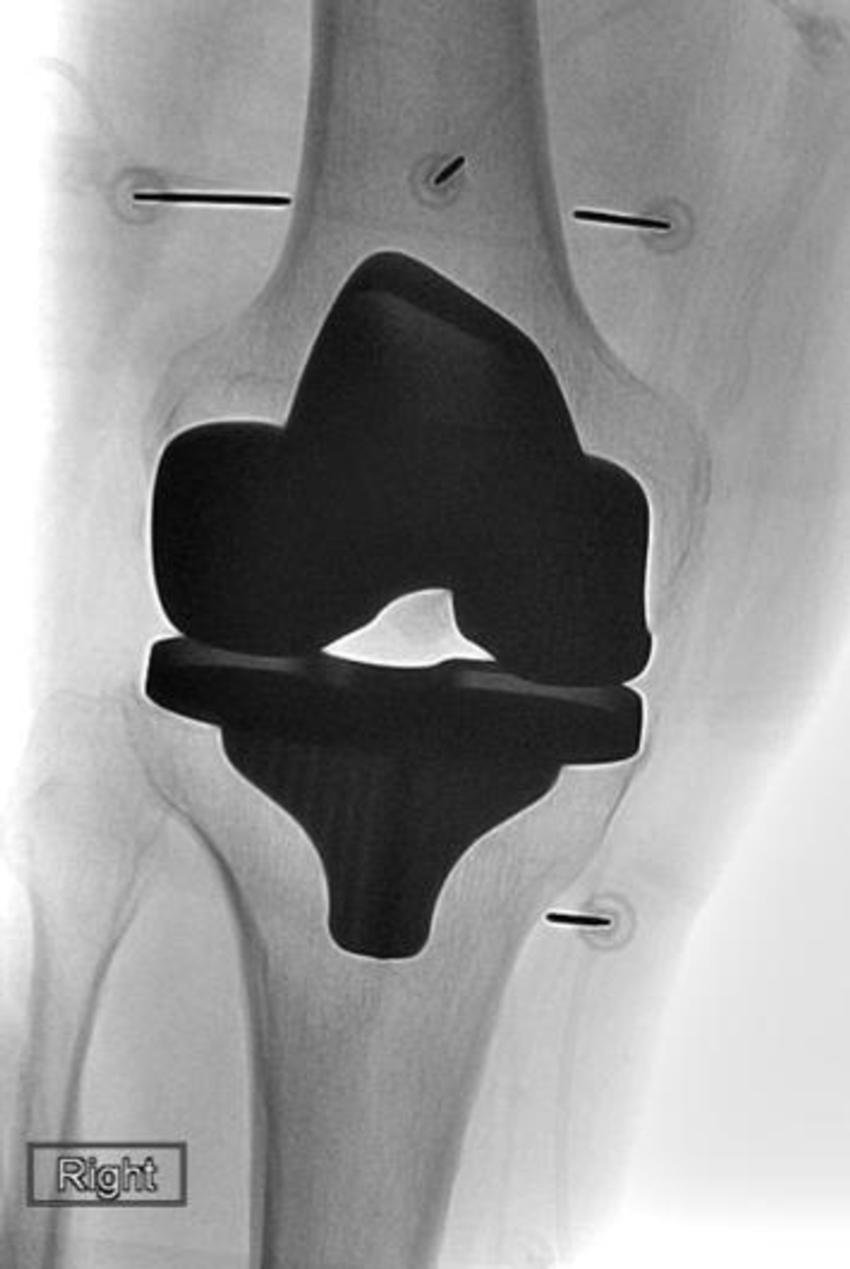

Figure 6. Image shows knee arthroplasty (replacement).

High-res (TIF) version